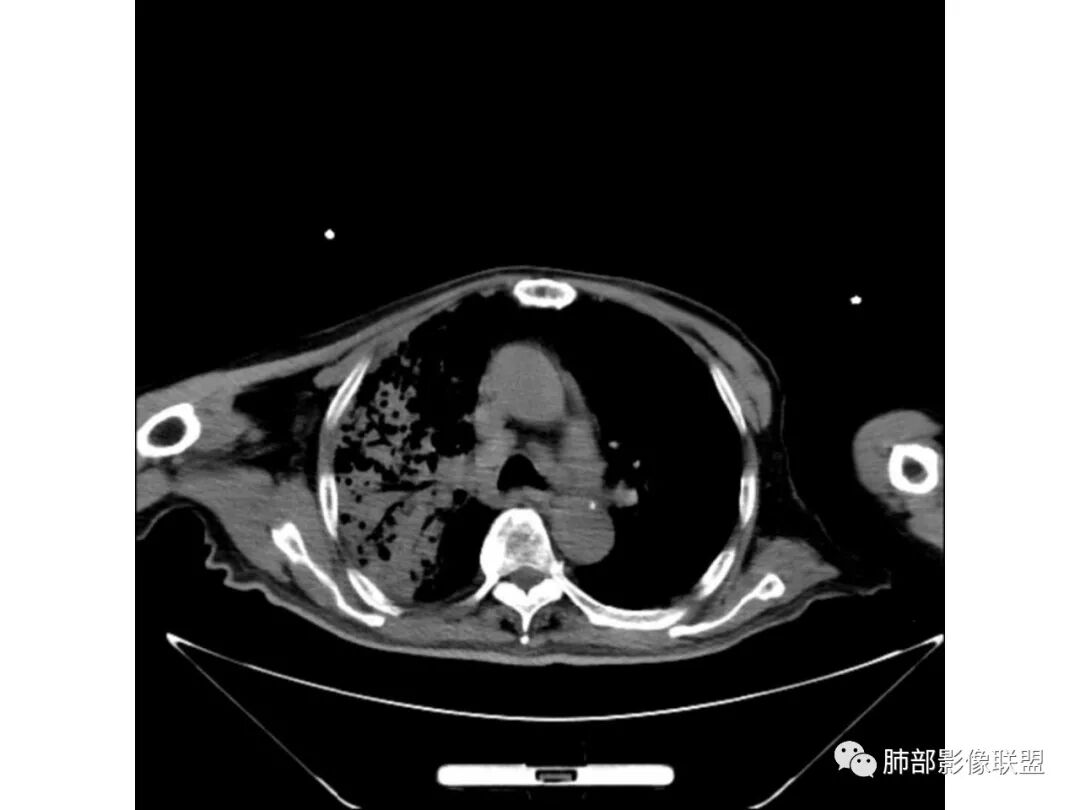

王秀仙:

右肺上叶大片实变,其内可见虫蚀样空洞及扩张支气管,其中一空洞内可见曲菌球样结构,右肺体积略缩小。老年糖尿病患者,慢阻肺背景,考虑右肺上叶干酪性肺炎并曲霉感染。

老年男性,糖尿病患者,右上肺大片实变,内可见多发虫蚀样空洞,右尖段近胸膜处一空洞内可见一类圆形结节影,支气管扩张,淋巴结肿大,双下肺索条,胸膜增厚。结合糖尿病病史,首选考虑结核干酪性肺炎合并曲霉菌感染,待排肺炎型肺癌

Shelia??:

老年男性,糖尿病10年,咳嗽气喘10天,肺气肿背景,右上肺大片实变影,内见虫蚀样空洞及空气支气管征,局部可见新月形空洞影,支气管局部欠光整,考虑感染性病变,结核?其内合并曲霉可能。